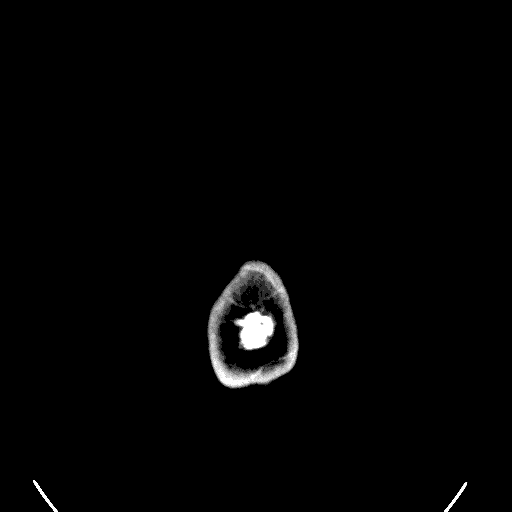

Virtual Autopsies

The socio-legal implications of virtual autopsies in coronial investigations